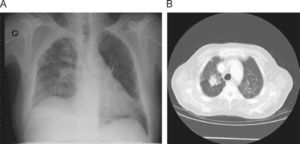

We present the case of a 79 year old man with a history of prostate a history of prostate cancer, arterial hypertension, chronic lymphatic leukaemia and atrial fibrillation. He is an ex-smoker (1 pack-year smoking history 20 years ago) and worked in a brewery for 27 years, having retired 9 years ago. He has been admitted with a respiratory infection and coughed up blood. On admittance BP: 160/70 mmHg. Heart auscultation detected arrhythmia of 120 beats per minute, respiratory auscultation found a general decrease of normal breathing sounds which were slight without any added noises. In additional tests requested it was noted that leukocytosis was 16,100/ul (neutrophils: 38%, lymphocytes: 50%), and there were no significant alterations of coagulation and biochemical values. A chest X-ray (fig. 1A) showed: Enlarged heart with signs of vascular reconversion, fibrous tracts of a residual aspect in the right upper lobe (RUL) and right para-tracheal node and a chest CT (fig. 1B) showed signs of pre-capillary hypertension, fibrous tracts in the apical region of the RUL. These findings had already been detected in previous studies 2 years before and had not worsened according to X-ray images. The Image was compatible with a 24×27 mm node in the RUL that contained a small cavitated image. Some mediastinal adenopathies of up to 15 mm in diameter were found in the precarinal region. The patient underwent a Mantoux test and bacterial testing (3 samples) that were negative. Clinical evolution was favourable with analgesic and antibiotic treatment, but given the smoking history, bloody cough and X-ray findings, a fibrobronchoscopy was performed. The most significant findings were vascular lacunae at the entry of the main right bronchus and some scar bands in the segmental bronchi of the URL bronchus. Respiratory function was normal on exploration. A PET scan was also performed which showed that a 29×35 mm node had formed in the URL with metabolism increase (SUV max 10.6) and changes in density, fibrous tracts and an increase in glycidic activity in the left upper and lower lobes, upper URL segment and middle lobe (SUV max 3.8,3.8,5.3, and 4.2, respectively). It was recommended that the histology of the node in the RUL be studied. A CT guided biopsy of the lung node was performed and the anatomopathological report stated that it was a proliferation compatible with lung silicoanthracosis.